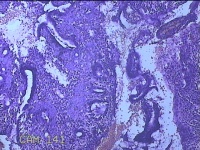

宫颈3点、9点、11点、12点组织

性别

女

年龄

37岁

临床诊断

人乳头瘤病毒感染

一般病史

HPV其他12型阳性

标本名称

大体所见

1.“宫颈3点组织”:灰白粉红色组织1x0.8x0.2cm一块。 2.“宫颈9点组织”:灰白粉红色组织0.7x0.5x0.2cm一块。 3.“宫颈11点组织”:灰白粉红色组织0.8x0.5x0.2cm一块。 4.“宫颈12点组织”:灰白粉红色组织8.5x0.5x0.2cm一块。

图4